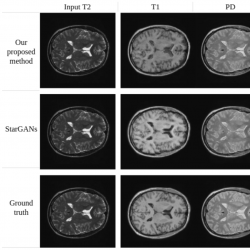

Fig. 19

Synthesis of MRA, PD-weighted and T1-weighted images using a single T2-weighted image as input (IXI dataset).

Figures

19 and

20 provide a qualitative comparison between the proposed method and Star-GAN in terms of multi-contrast synthesis. The results demonstrate that Star-GAN partly fails to capture structural and perceptual similarities for small anatomical regions, which are effectively captured by the proposed method. In Fig.

19, the synthesis of MRA from a T2-weighted image shows that Star-GAN struggles to reproduce the accurate colour of the image, while the proposed method successfully generates an image that is nearly identical to the real one. Similarly, Fig.

20 with FLAIR contrast.